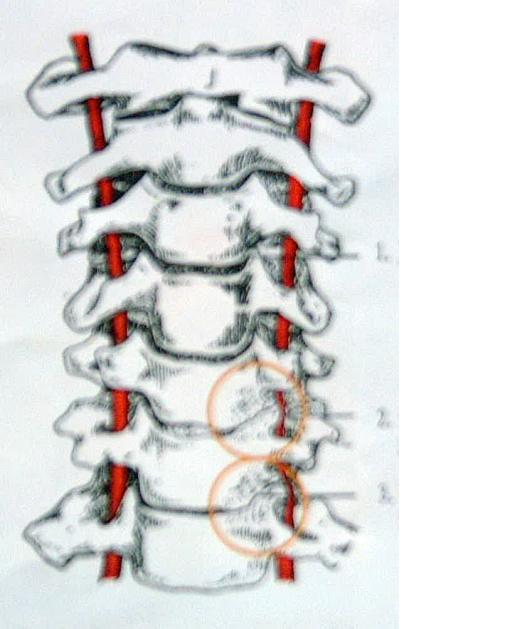

“颈椎”病,顾名思义,是(颈椎)“骨头”出毛病了,

如果不去治疗“骨头”,却把“肌肉”拿来治疗(见下图),那怎么能治好颈椎病呢?

答:因为脖子里的“骨头”,与“神经”是紧挨着的。(见下图)

现代科学研究发现,颈椎病的发病机理是: (1)颈部“队列”变形,刺激或压迫到了神经(或血管); (2)被挤压的这条神经肿胀、发炎; (3)这条发炎的神经所管理的肌肉产生痉挛并疼痛,或这条发炎的神经所管理的器官的功能失常。 可见,上述的“因果关系”是:

颈椎“队列”变形——→神经受压并发炎——→肌肉“发紧”并酸痛或器官功能失常。 所以,队列变形是“因”,神经发炎是“果”,其他部位症状(如:肌肉酸痛)是“果”引起的“果”。